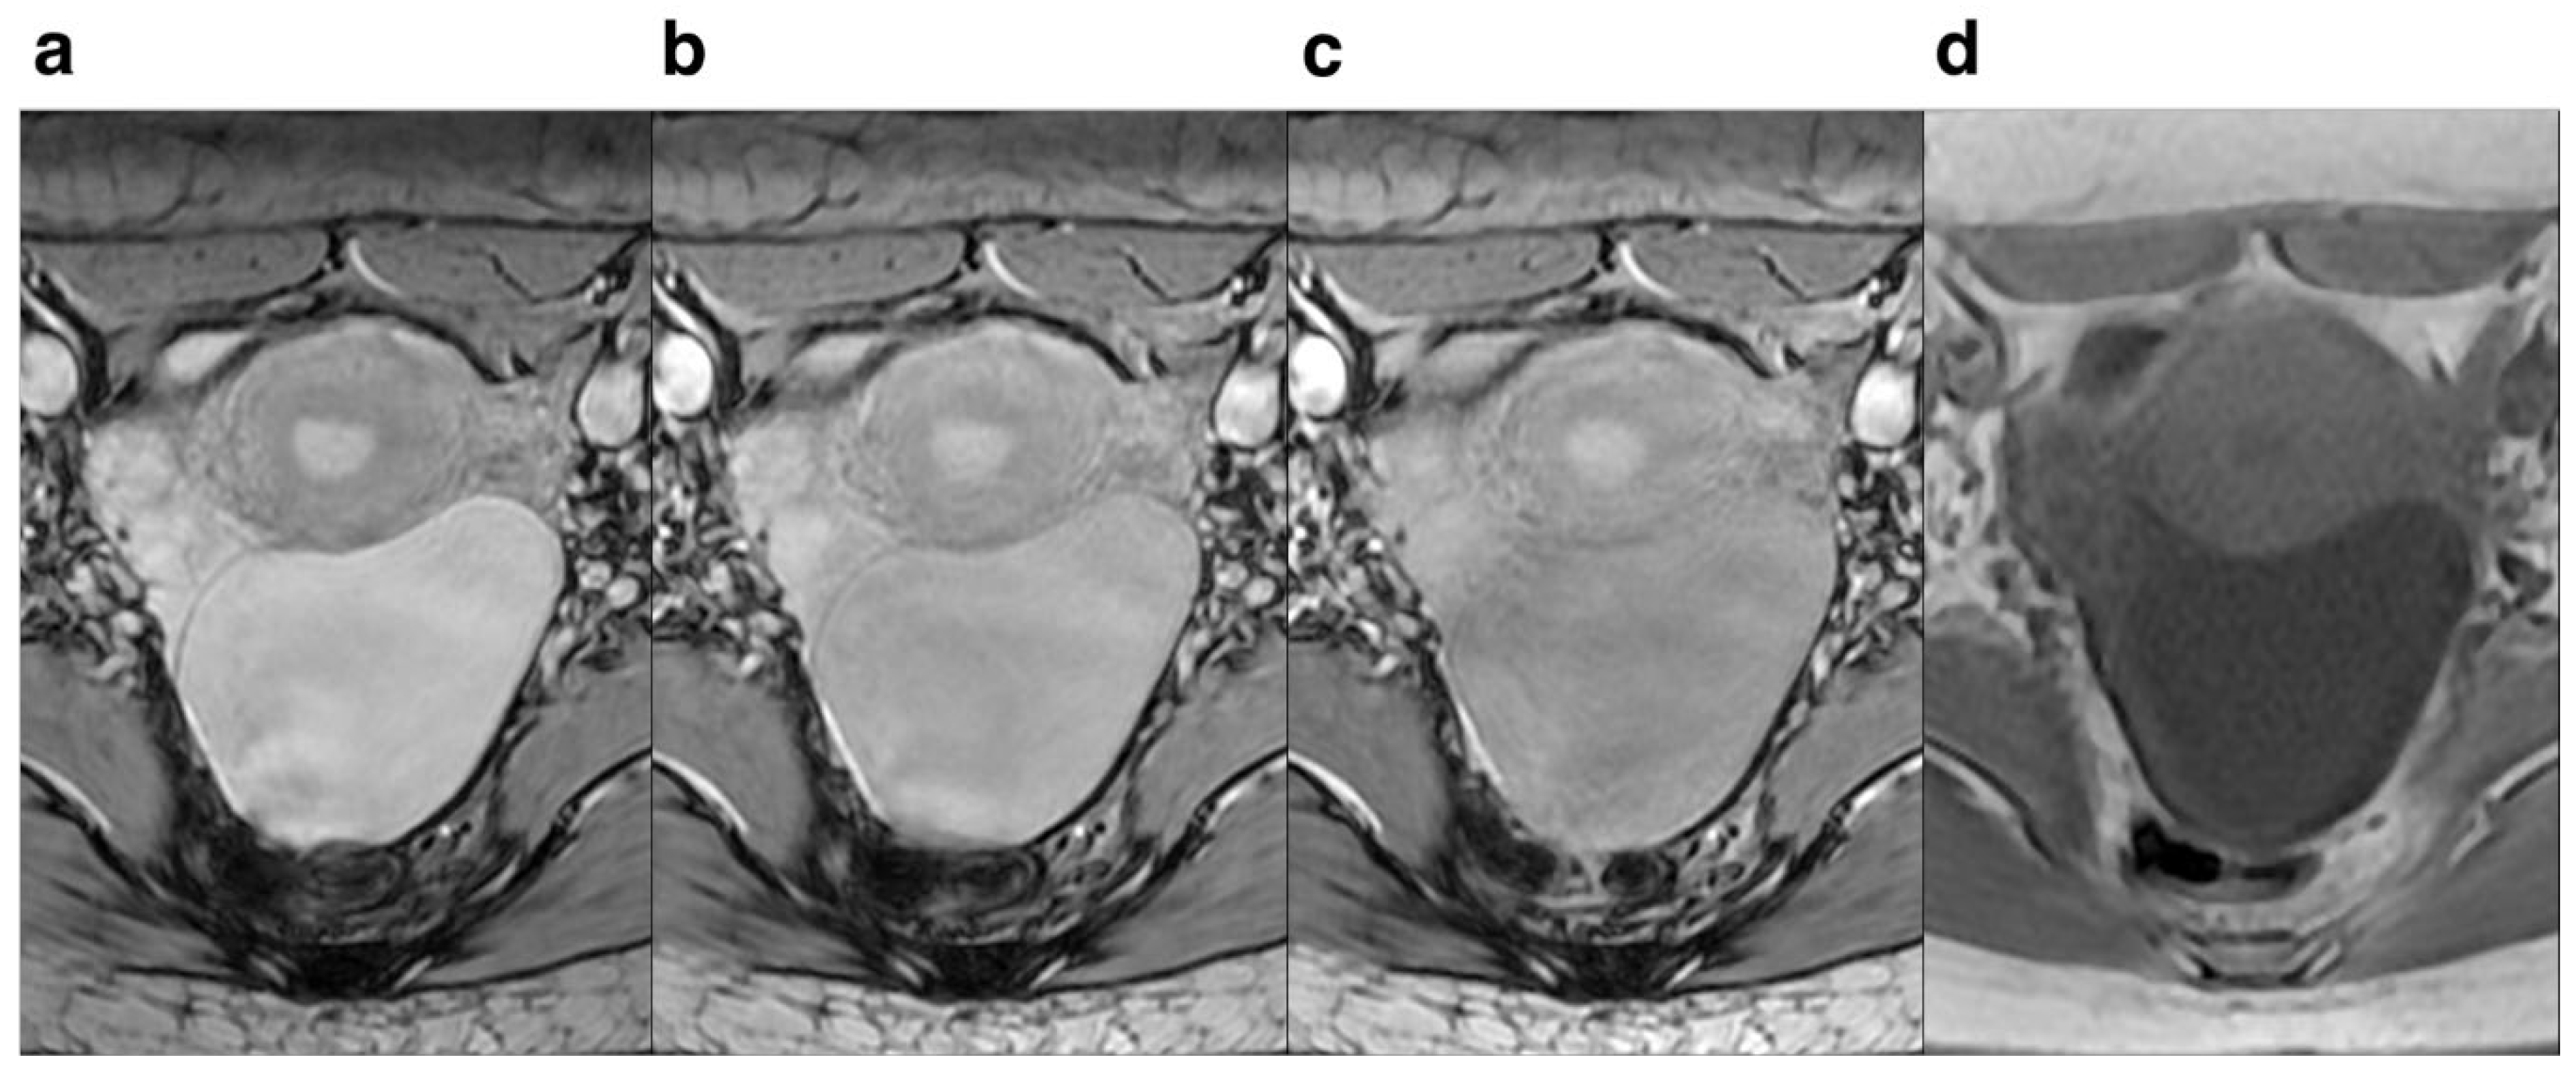

Figure 4. Female, 83 years old. Pelvic cavity under each FA is shown. SWI sequences FA were 10° (a), 15° (b) ,20° (c) and T1WI (d),respectively. It can be seen that when FA=10°, the pelvic structure has less deformation and less artifacts than the other FA.

Regarding FA, lower FA revealed more anatomical detail and lesion clarity, less deformation and artifacts, and 10° had the best effect compared to 15° and 20°. The score for anatomical details and lesion clarity for FA=10° were significantly higher compared to those of FA=15° and 20°, indicating that the anatomical details and lesion clarity were highest at 10° (Figure 3). For the degree of deformation and ghosting, the subjective rating for FA=10° was higher than that of FA=15° and 20°, suggesting that the degree of deformation and ghosting was smallest at 10° (Figure 4), while the degree of deformation and ghosting was the most severe at 20°. Qualitative assessment revealed superior image quality at a FA of 10° compared to 15° and 20°. Images acquired at FA=10° demonstrated improved visualization of small hemorrhagic lesions, clearer delineation of peritumoral infiltration in tumors, and enhanced depiction of pelvic anatomical structures. Moreover, image quality was superior in the FA=10° scans compared to FA=15° and 20° scans, likely attributable to the substantial difference in signal intensity between focal lesions and surrounding tissues. This heightened level of detail is crucial for accurate diagnosis and selection of optimal treatment strategies.